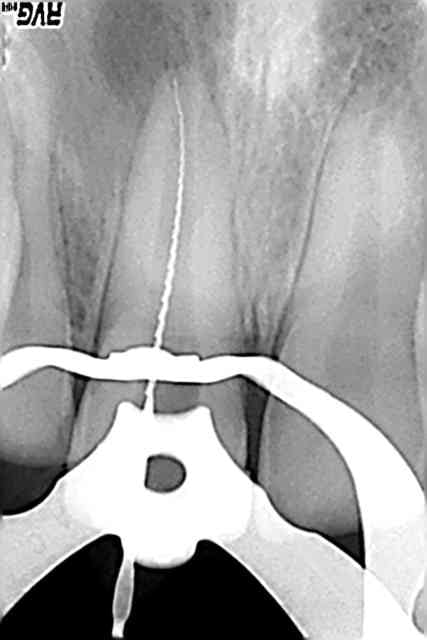

Je viens de traiter une jeune fille de 17 ans, qui a fait une cellulite suite à une nécrose sur 11.

La dent a subi un traumatisme (cheval) il y a 7 ans avec certificat initial et réparation de l'angle au composite, à l'époque.

Malheureusement, la dent était nécrosée. Elle a été vue par le confrère de garde dimanche dernier qui a ouvert la chambre. J'ai fait l'endo aujourd'hui.

Digue, irrigation importante, j'ai eu du mal à instrumenter, je flottais à l'apex. Le protaper F4 travaillait à peine à l'apex. En manuel je n'ai rien au dessus de 50. La dent est évidemment immature.

Pour obturer, j'ai coupé mon cone de 5/10eme en 5/10eme jusqu'à obtenir une butée. Je l'ai eue à 70/10èmes...

J'ai ensuite obturé de façon classique, j'ai même inséré le thermocondenseur à LT-5mm. Bref j'ai fait au mieux de mes capacités.

La question que je me pose est celle de la longévité d'une dent immature avec un traitement qui me parait satisfaisant. 10 ans ? 20 ans ?